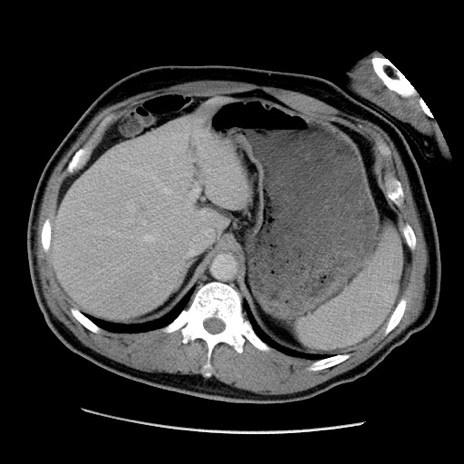

症例22(横断像)

【症例】50歳代男性

【主訴】腹痛

【現病歴】AVMからの被殻出血のため回復期リハ病棟入院中。 本日午後3時頃急に下腹部痛が出現した。

【既往歴】AVM、被殻出血、虫垂炎、高血圧

【身体所見】意識晴明、左半身不全麻痺、会話の理解は良好、36.5°C、腹部:膨隆、全体に板状硬、下腹部正中に圧痛点あり、反跳痛-、筋性防御不明、右下腹部にope scar

【データ】WBC 9400、CRP 0.06